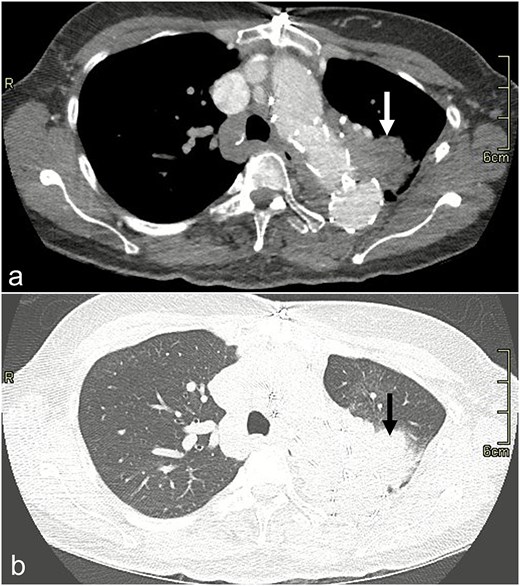

In 2022, she was admitted for recurrent hemoptysis. Bronchoscopy revealed a small amount of blood and inflammation in the left upper lobe (LUL), but no infectious source was identified on culture. Consolidation was identified on computed tomography (CT) in the LUL, which was suspicious for erosion of her graft resulting in pulmonary hemorrhage (Fig. 1). However, her hemoptysis decreased on antibiotics. The possibility of a fistula from her aortic graft to the lung parenchyma was raised, but an infectious process was favored due to her antibiotic response.

CT scan image with dissection protocol of the left upper lobe consolidation (arrow) on (a) mediastinal and (b) lung windows.